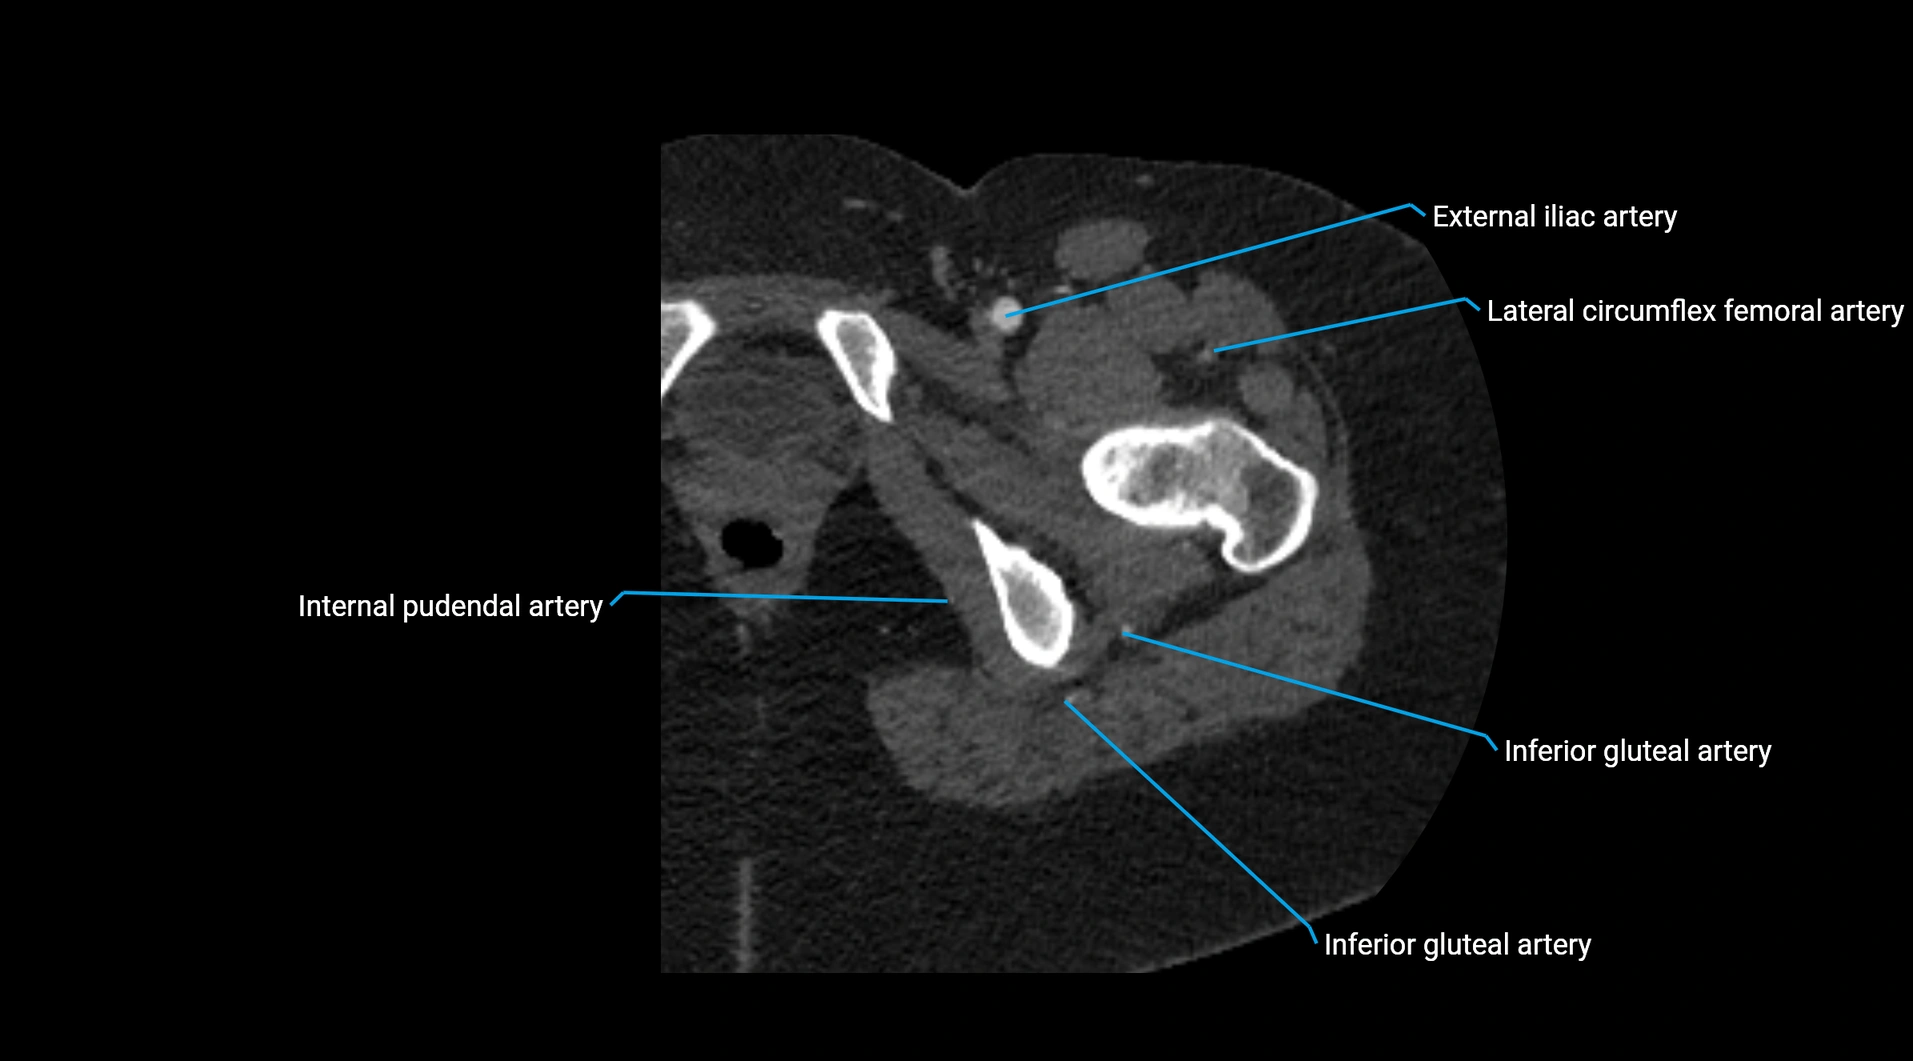

Contrast-enhanced CT (CTA):

• Gold standard for abdominal aortic imaging

• Provides excellent detail of lumen, wall, aneurysm, thrombus, and branch vessels

• Multiplanar and 3D reconstructions help in aneurysm measurement, stent graft planning, and dissection evaluation

• Detects acute rupture, traumatic injury, or occlusion with high sensitivity